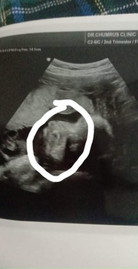

แม่ๆๆคะแบบนี้คือจมูกลูกผิด ปกติหรือป่าวคะพอดีพึ่งเห็นใบ ซาวด์แต่หมอก็ไม่ได้พูดอะไรแต่แม่กังวนมากเลยคะ

ยังจิ๋วเดียวเองค่ะ ยังเป็นลูกอ๊อดอยู่เลย ดูแทบไม่ออกนะคะ อย่าเพิ่งกังวลไป อายุครรภ์แม่น่าจะยังไม่มาก 😊